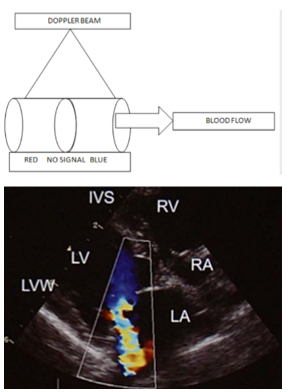

Describe doppler.

Cells moving toward the transducer reflect an increased number of sound waves so the received frequency is greater than the transmitted frequency. This is positive frequency shift.

Cells moving away from the transducer reflect fewer sound waves, and the received frequency is less than the transmitted frequency. This is a negative frequency shift.

In Color Flow Doppler Imaging the velocity and direction of blood flows are depicted in a color map superimposed on the B-mode image.

Allows for detection and analysis of moving blood cells or myocardium and provides hemodynamic information.